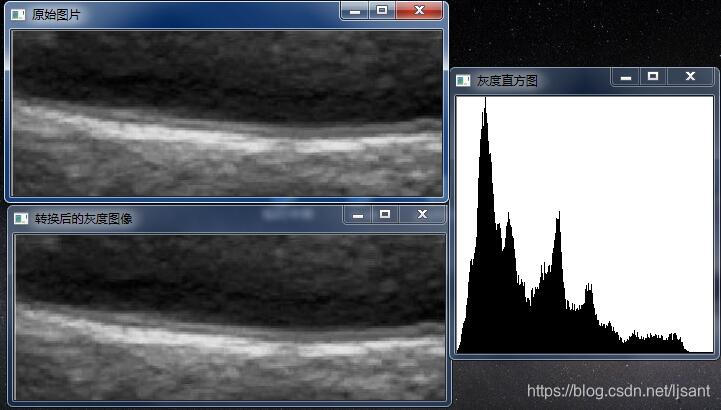

1)灰度直方图

直方图一般的定义都是灰度直方图(针对与灰度图像),opencv2中可以绘制灰度直方图的函数:calcHist();这有着很多重载函数,最常用的一种形式:

当然我们也可以根据Mat类写一个自己函数统计如下:

void Hist(cv::Mat &image){int table[256] = { 0 };int nr = image.rows;int nc =image.cols*image.channels();for(int j =0;j<nr;j++){uchar * data =image.ptr<uchar>(j);for(int i=0;i<nc;i++){table [data[i] ]++;}}double max = 0;int sum = 0;for (int i = 0; i < 256; i++) {sum += table[i];if (table[i] > max)max = table[i];//找到最大频次出现的数}Mat histgram(256, 256, CV_8U, Scalar(255));for (int i =0; i <=255; i++){line(histgram, Point(i, 255), Point(i, (255 - table[i]*255/max)), Scalar(0));}imshow("灰度直方图", histgram);

}

2)灰度均衡(直方图均衡)

在1)的情况下,开始用均衡的手法。我的理解所谓灰度均衡:是为了转换后的直方图是平的,满足每一个灰度级上有相同像素点的输出图像,但是实际过程中不会出现类似一条平的直方图,因为像素点最多只有256,太少。经过一些列的计算公式